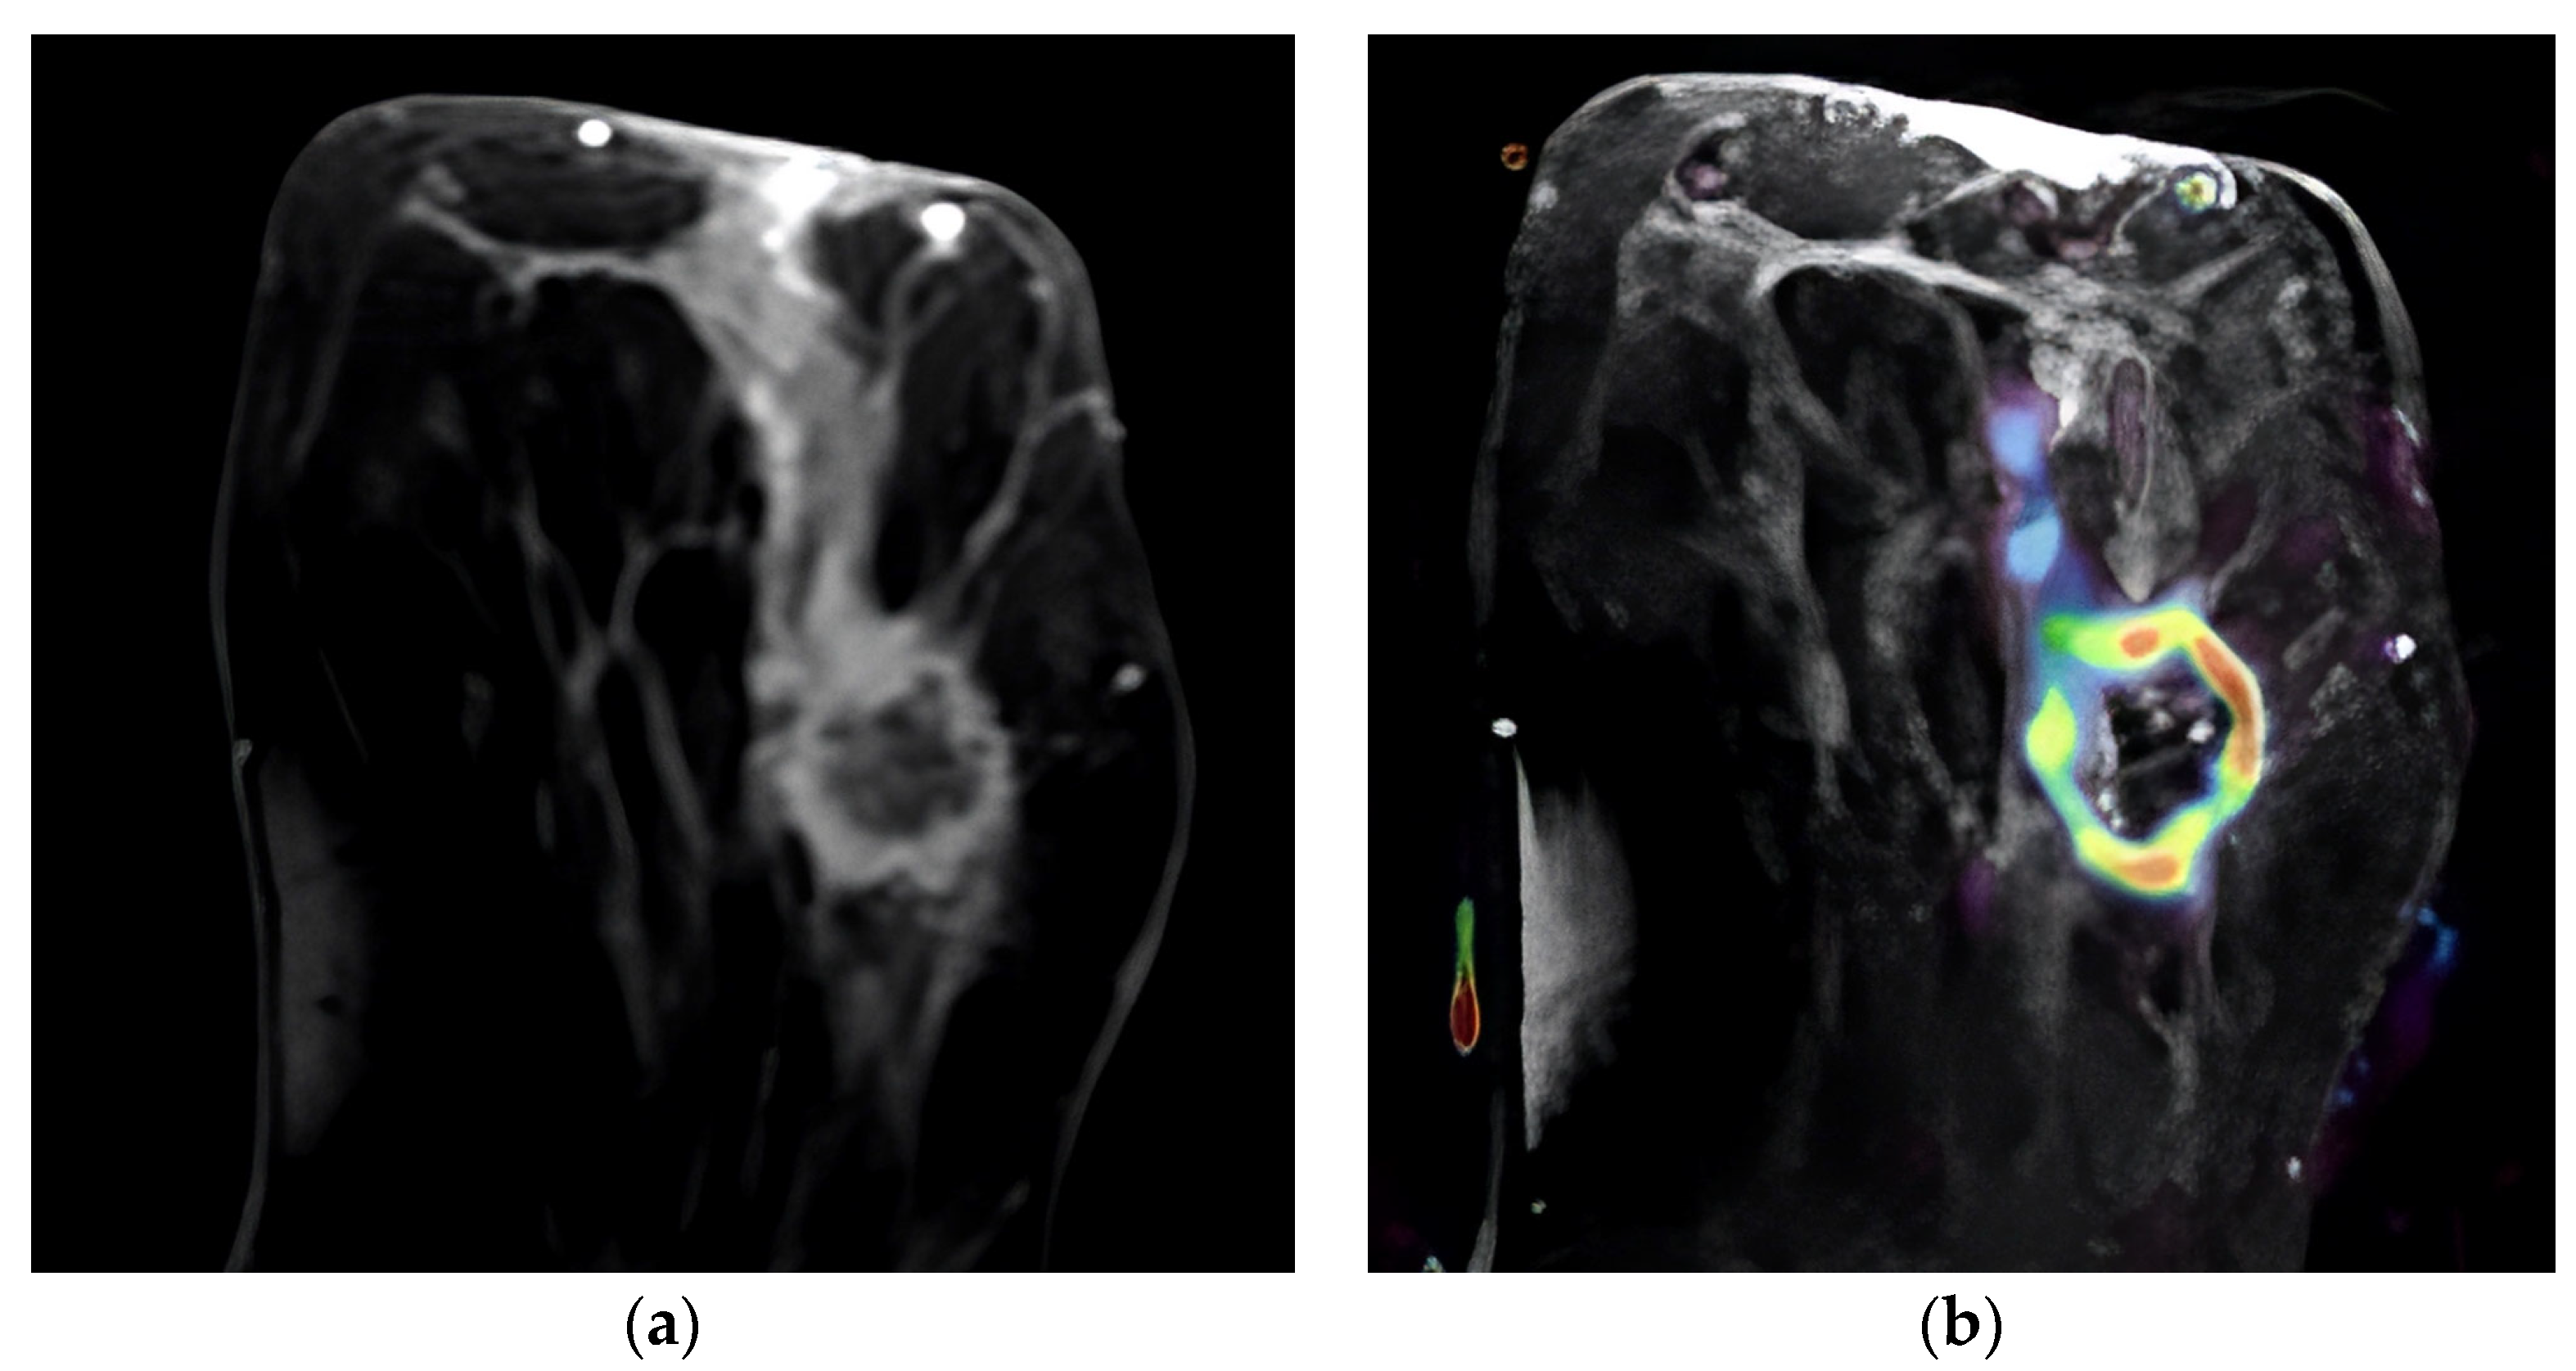

Figure 2.

T2-weighted MRI image that shows the tumor’s location in the axial slice (a). Perfusion mapping (red shows elevated perfusion) and progressive contrast change show washout in the tumor’s periphery (b).